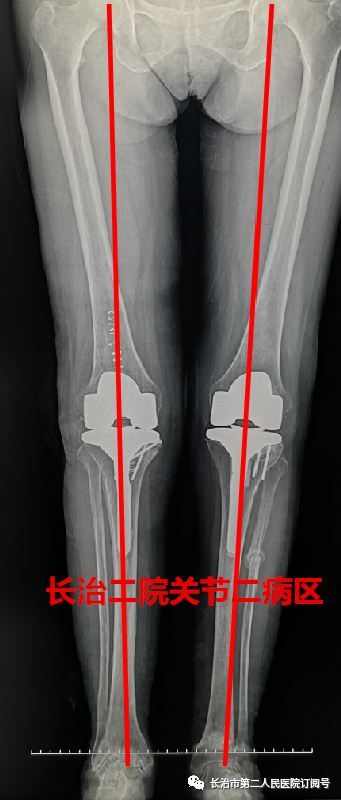

走路 在常人来看 是件多么轻松的事情 可对于李老太来说 近日,长治二院骨科关节二病区来了一位严重类风湿性关节炎患者,疾病困扰了她13年,日常行走已经很困难了。 长治二院骨科关节二病区 雷晓宇医师团队妙手回春 完美实施双膝关节置换术 随即轻松行走! 对李老太来说 走路成为了一种享受 今年69岁的李老太在13年前双膝先后出现疼痛无力的症状,但随着年龄的增长病情逐年加重,双腿关节等处都严重变形。双膝并拢时成“顺风腿”畸形,行走也变得相当困难,行各种保守治疗方案效果差,双膝疼痛行走受限,严重影响了日常生活。 图为:术前MRI及CT 图为:术后X片 据李老太的主管医生朱彦伟副主任医师介绍“重度外翻性膝行膝关节置换,由于其软组织不平衡及存在严重的骨缺损,手术难度极高,对于关节外科医师而言,绝对是充满挑战性事件! 入院后,骨科关节二病区雷晓宇医师团队术前进行仔细的手术规划,充分的术前准备,为李老太制定个性化治疗方案,对存在不同严重畸形的双膝分别行人工膝关节表面置换术。术后第二天就可以在助行器的保护下下床行走。经过精心的康复治疗,目前李老太的行走步态正常,生活质量明显提高。科室医护人员对李老太住院期间的精心治疗和护理,更是让老人及家属感受到了长治二院医护团队的专业素养和暖心服务。 对于像李老太这样的类风湿性关节炎患者,长治二院骨科关节二病区雷晓宇主任特别提醒:一旦出现疼痛、关节畸形、保守治疗无效后,应尽早行膝关节置换。 朱彦伟 关节二病区副主任医师 朱彦伟医师:周四全天门诊 电话:158 3551 0903 ■ 直通大医院丨9月18日长治二院关节外科一病区主任张鹏为您讲解《股骨头坏死的预防与诊治》 ■ 皮肤病患者的福音——又一“名医工作室”落户长治二院!!! ■ 长治二院特邀北京大学第一医院皮肤科教授陈喜雪来院指导讲学 供 稿丨朱彦伟 视 频 | 朱彦伟 编 辑丨张静晗 审 核丨雷 赫